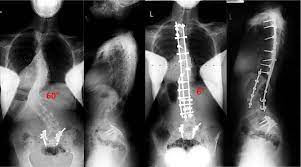

Surgical Treatment Of Spinal Deformities In Marfan Syndrome Long Term Follow Up Results Using Different Instrumentations Palmisani M Dema E Rava A Palmisani R Girardo M Cervellati S J Craniovert Jun Spine